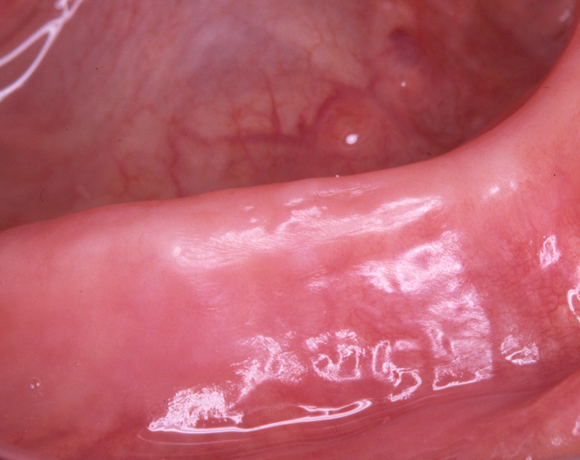

Solcoseryl Salbe eignet sich durch seine anäthesierende Wirkung besonders auch bei schmerzhaften Druckstellen.

Nach einer Woche ist die entzündete Fläche vollständig verheilt.